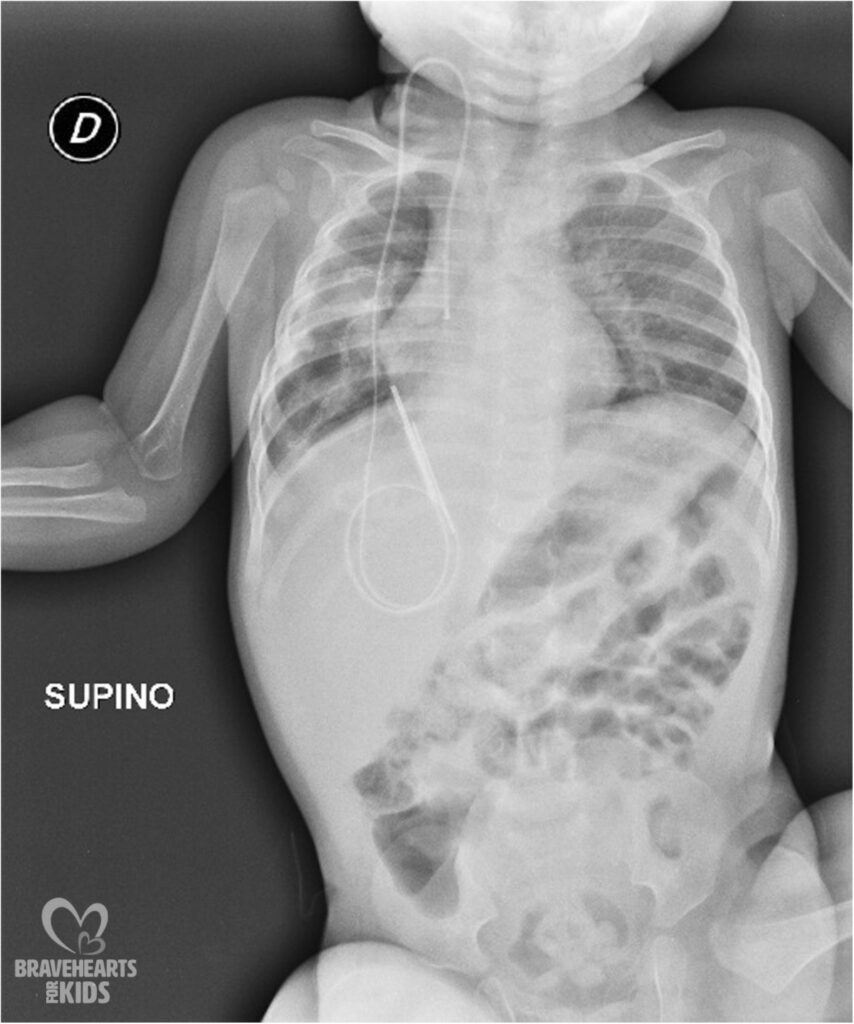

Pleuropulmonary blastoma (PPB) is a rare malignancy of childhood. It often represents a manifestation of a hereditary tumor predisposition syndrome (DICER1 syndrome). Because of its malignant potential, surgical resection of cystic lung lesions is recommended in germline DICER1 mutation carriers. We present a case of a 3-year-old male child with type III PPB successfully managed with ifosfamide, vincristine, actinomycin-D, and doxorubicin (IVADo) chemotherapy and surgery. A heterozygous germline pR688X mutation of DICER1 gene was demonstrated. Six years after primary diagnosis, several small lung cysts remained stable without further therapy. The management of residual asymptomatic lung cysts represents a clinical challenge in these patients.